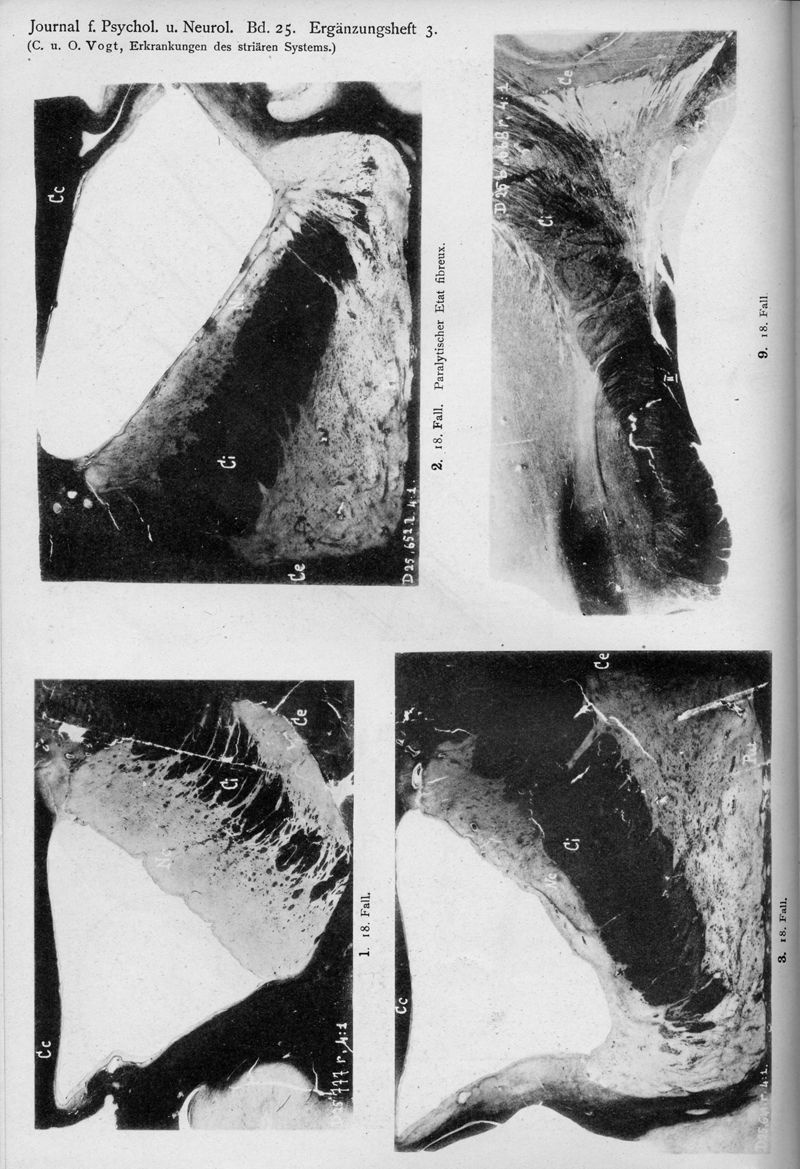

VOGT, Cécile / VOGT, O.

In : Journal für Psychologie und Neurologie,

1920, Vol. 25, pp. 627-846